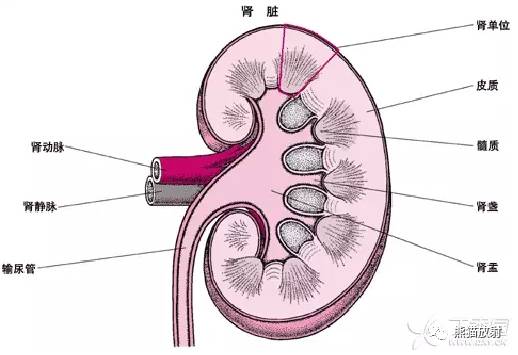

髓质海绵肾(MSK)多散发,是指肾髓质及肾乳头部分的集合管发育不良并扩张,大部分情况下,可合并髓质肾结石。偶尔具有遗传性。

横切面上,肾脏表现为海绵样,在肾锥体可见多发小囊腔。囊内包含黄棕色液体及脱落细胞或钙化物质;囊内结石,囊壁包含草酸钙有或无磷酸钙。

可双侧(75%) 或单侧(25%),可累计单个或部分肾锥体;